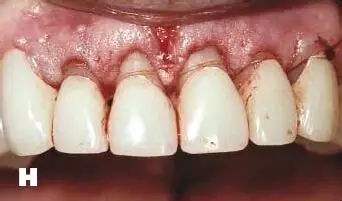

三、修復治療及松牙固定術

牙齒松動疼痛妨礙修復體咀嚼功能、炎癥性的牙周組織損害基牙、牙周炎癥時牙齒位置不穩(wěn)定、牙齦炎癥未消除取模不準確、修復體冠邊緣必須建立在健康牙齦溝內(nèi),通過修復治療,恢復牙周組織功能。對于能夠保留的松動牙齒,有必要進行松牙固定術。